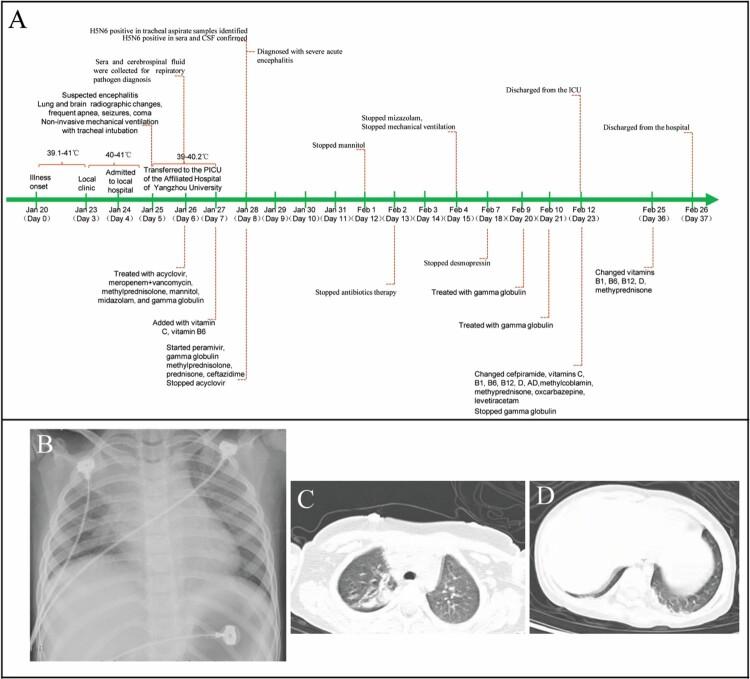

Highly pathogenic avian influenza viruses (HPAIV), such as H5N1, H5N6, and H7N9, have been reported to frequently infect humans, but acute encephalitis caused by HPAIV in humans has been rarely reported. We report the first critical case of acute encephalitis with mild pneumonia caused by the H5N6 virus. On January 25 of 2022, a 6-year-old girl with severe neurological symptoms was admitted to our hospital and rapidly developed into seizures and coma. Brain imaging showed abnormalities. Electroencephalogram (EEG) presented abnormal slow waves. Cerebrospinal fluid (CSF) contained elevated protein (1.64 g/L) and white cells (546 × 10/L). Laboratory investigations revealed abnormally elevated transaminases, lactate dehydrogenase, and cytokines in serum. A novel reassortant H5N6 virus was identified from the patient's serum, CSF, and tracheal aspirate specimens. Phylogenic analysis indicated that this virus was a novel reassortant avian-origin influenza A (H5N6) virus that belonged to clade 2.3.4.4b. This patient was diagnosed with acute encephalitis and discharged from the hospital accompanied by a language barrier. An epidemiological investigation confirmed that wild waterfowls were the direct source of infection in this case. Our study highlights the urgent need to pay attention to acute encephalitis caused by HPAIV.